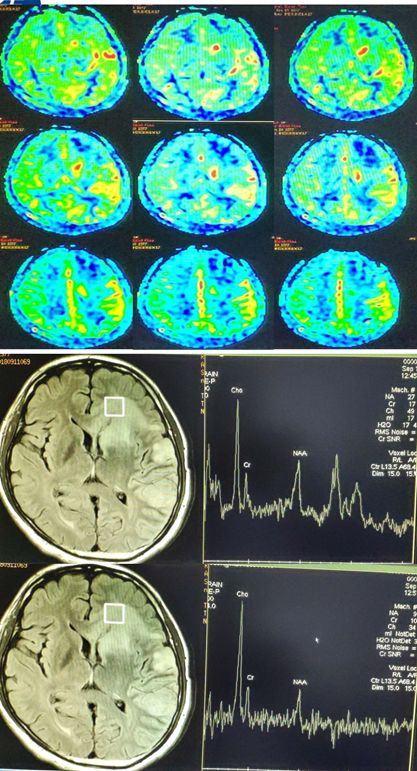

诊断依据:①右侧半球;多灶性,轻偏瘫,认知下降;②视频脑电图(VEEG):EPC,PET:右侧半球代谢减低;抗癫痫药物疗效差;③术后病理:脑组织小胶质细胞和T细胞浸润。

Rasmussen脑炎:为单侧性大脑半球受累为主的进展性疾病,常规抗癫痫药物治疗无效,局灶性发作为其主要特点,部分性癫痫持续状态(EPC)为其发作的主要表现形式,多伴有受累侧半球相关的运动和认知功能减退。RE主要的病理特点:局限于受累大脑半球的炎性疾病,以T细胞浸润、小胶质细胞增生、小胶质结节形成,以及随后出现的神经元脱失、星形细胞增生等为主要表现形式。MRI特点岛叶及岛叶周围出现轻度局灶性大脑皮质萎缩;同侧脑室扩大;大脑皮质和(或)皮层下T2和FLAIR像的高信号;尾状核头部信号增高或萎缩。在上述改变未发生之前可先出现一过性大脑皮质局部肿胀。

灌注成像,病灶这一块有高有低,像是病灶核心有点高灌注,水肿的地方低灌注。波谱也只能提示神经元受损,有一点脂质波,没有很强的特异性。DWI高,似乎支持淋巴瘤。没想到结果出来却是结核性肉芽肿。